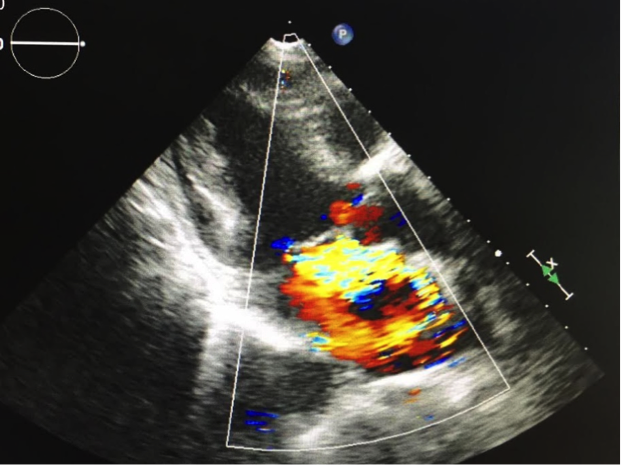

これは僧帽弁閉鎖不全症の患者さんの心臓です。左心室から左心房へと血液が逆流していることがわかります。

(提供:ニューハートワタナベ国際病院)